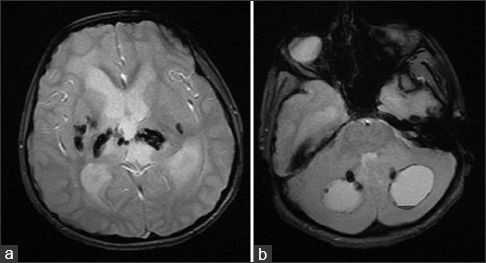

На МРТ головного мозга определялись обширные области гиперинтенсивного в Т2ВИ и FLAIR сигнала, которые затрагивали перивентрикулярные области белого вещества, оставляя интактными U-волокна и мозолистое тело с кистозными включениями и признаками обструктивной гидроцефалии. Обнаруженные ранее на КТ кальцинаты были гипоинтенсивны в Т2- и Т1ВИ и показывали «выпадение» МР-сигнала в GRE.

На аксиальных Т2ВИ (a, b) и FLAIR (с, d) томограммах можно увидеть обширные области гиперинтенсивности белого вещества мозга, что говорит о лейкоэнцефалопатии.

Аксиальные Т1 и Т2ВИ сканы демонстрируют кисты в обеих гемисферах мозжечка, расположенные над третьим желудочком в пинеальной области; обратите внимание на расширение боковых желудочков в результате обструктивной гидроцефалии.

Области “выпадения” МР-сигнала на GRE в области базальных ядер, таламусов и ядер мозжечка соответствуют кальцинатам.